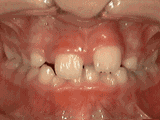

Patient's parents were concerned about both aesthetics and the health of the erupting permanent

teeth when they brought him to the orthodontist at age eight. The lower front teeth were crowded and they

touched the palate, and the upper front teeth were extremely displaced from their normal positions.